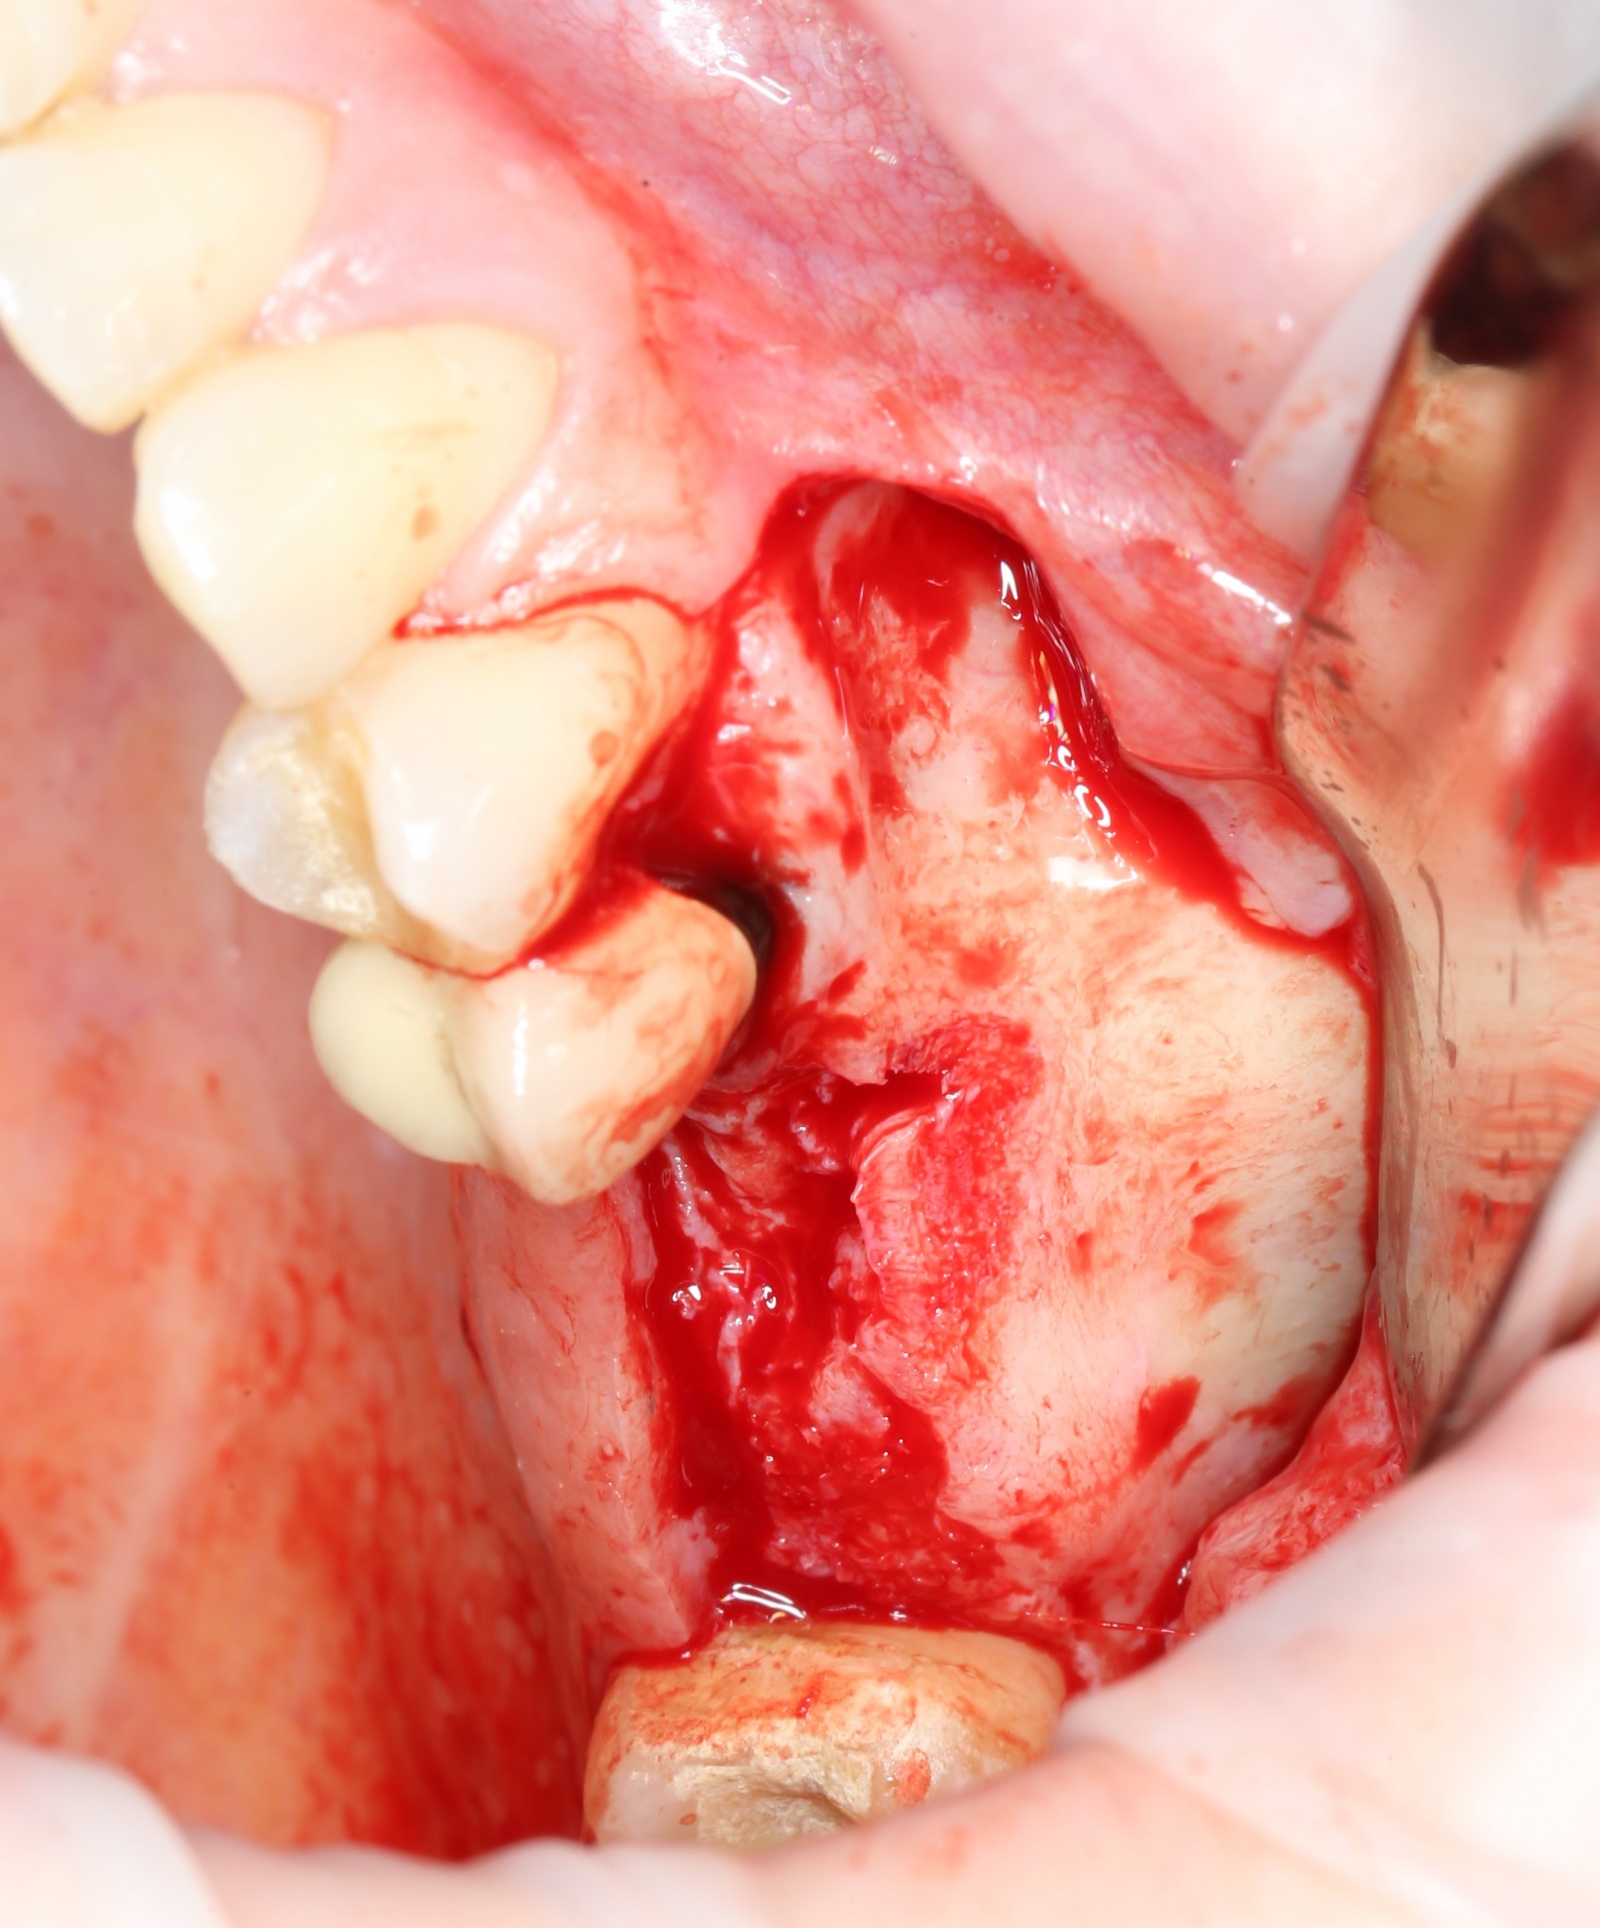

После того, как анестезия подействовала, при помощи скальпеля производится разрез, а распатора — скелетирование кости (отделение надкостницы от компактного вещества кости).

Разрез:

Скелетирование кости:

Мной и ортопедом было принято решение по удалению пятого зуба, потому как перелечить его будет, к сожалению, невозможно.

Удаления зубов, как правило, проводится при помощи специального инструмента – элеватора, а не щипцов, как многие думают.

Конечно, щипцы тоже используются, но зачастую, можно обойтись и без них.

«Вжух»:

Лунка моментально заполняется кровяным сгустком.